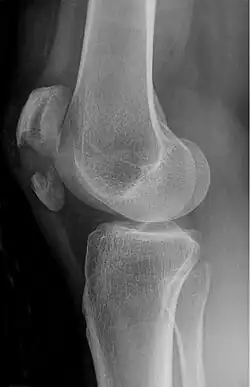

| A fracture of the patella seen on a lateral view | |